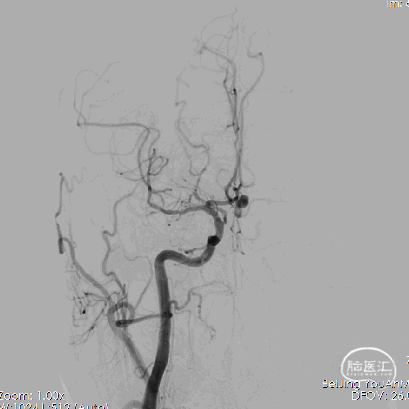

1、右侧颈内动脉造影提示双侧大脑前动脉显影,前交通动脉可见动脉瘤。

2、行右侧压颈试验后左颈内动脉造影示左侧大脑前动脉未见显影。

3、行左椎动脉造影示左侧大脑前动脉供血区可见浅淡显影。

4、工作位测量:瘤颈长约3.94mm,瘤体大小约9.09×7.40mm,主瘤体上可见三个子瘤大小分别为:3.84×2.43mm、3.09×2.54mm、3.39×2.44mm。